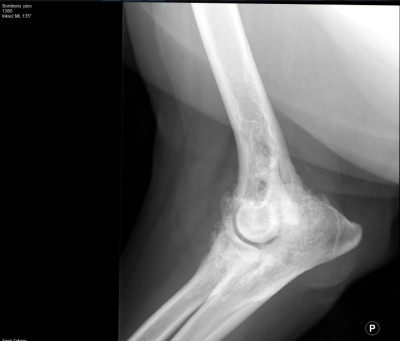

Przednie łapki Bamberka są w tragicznym stanie. Ma on bardzo ograniczoną ruchomość, praktycznie nie może zgiąć łokci. Psiak cierpi na dysplazję łokciową i zaawansowaną artrozę stawów łokciowych (prawdopodobnie już jako kilkumiesięczny psiak nieprawidłowo stawiał te łapki ale jego „właścicielowi” pewnie przez myśl nie przeszło, żeby go diagnozować :( )

Łokieć 1.jpg

Plik ściągnięto 12 raz(y) 28.18 KB